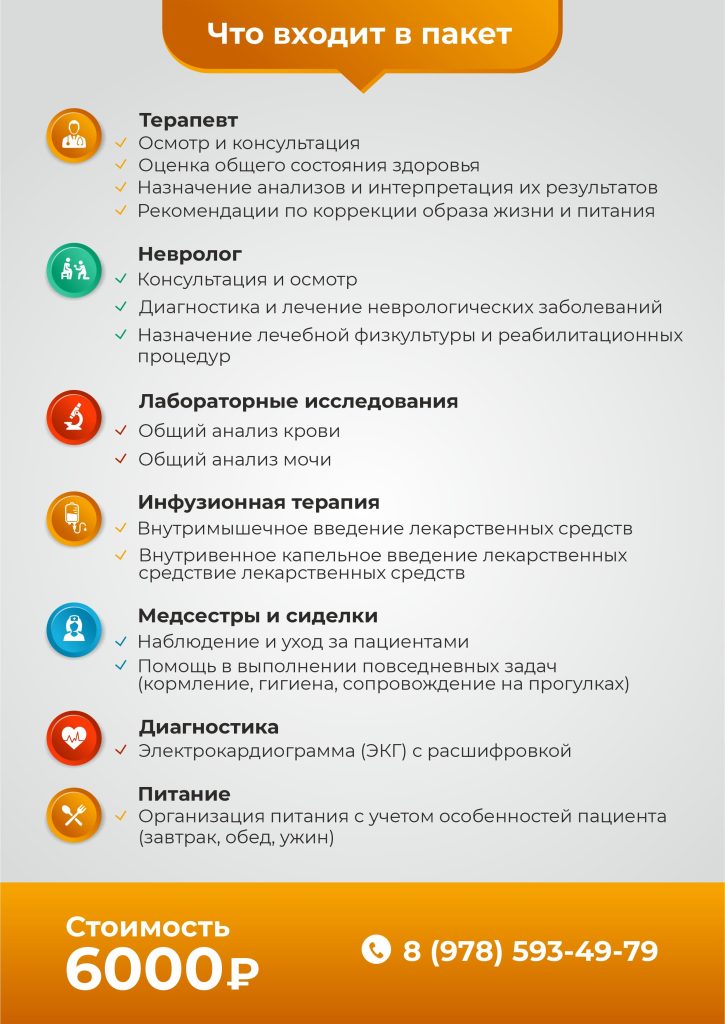

Этот пакет представляет собой наиболее комплексную программу восстановления, включающую полное медицинское сопровождение, расширенные анализы и физиотерапевтические процедуры.

Количество мест ограничено, воспользуйтесь возможностью пройти курс по сниженной цене.

Этот пакет идеально подходит для пациентов с хроническими заболеваниями, которые нуждаются в постоянном мониторинге и поддержке.

Программа включает дополнительные процедуры и регулярные осмотры врачей для поддержания стабильного состояния здоровья.

Этот пакет предназначен для тех, кто нуждается в регулярном мониторинге состояния здоровья.

Он идеален для профилактики и ранней диагностики, предоставляя основные медицинские услуги для поддержания стабильного состояния.

Программа VIP-реабилитации — это максимальный комфорт, индивидуальный подход и исключительный уровень медицинского обслуживания. Каждая деталь программы создается с учетом ваших личных потребностей, а премиальные услуги обеспечат вам наиболее эффективное и комфортное восстановление. Все включено, включая уникальные VIP-услуги, которые помогут вам быстрее вернуться к полноценной жизни.

В пакет входят все услуги из пакета «Комплексная реабилитация»

Консультации специалистов: терапевт, невролог, кардиолог, реабилитолог, психолог.

Лечебная физкультура, массаж, механотерапия, парафинотерапия.

Лабораторные исследования: общий анализ крови, общий анализ мочи, биохимический анализ крови, клинический анализ с лейкоцитарной формулой.

Круглосуточный уход и помощь сиделок.